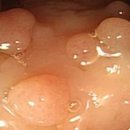

​ 영등포병원 대장내시경 후기 30살에 용종제거⁉️ 영등포병원 ⏰월-금 08:30-17:30 토요일 08:30-12:30 일요일 정기휴 ☎️ 02-2632-0013 영등포병원 서울특별시 영등포구 당산로31길 10 영등포병원 안녕하세요 30살에 대장내시경하고 용종 뗀 사람의 대장내시경 후기입니다 식단 저는 서울 영등포병원 건강검진 센터에서...

으로 건강검진을 받고 왔습니다 위, 대장 내시경 포함해서 받고 왔는데 저번엔 다른 병원 건강검진받았었는데 여기도 괜찮더라고요 ​ 대장 내시경 준비~건강검진 후기 시작해 볼게요! ​ 대장 내시경 준비 검진 12시간 전~ Previous image Next image 대장 내시경을 받으시는 분들은 1주일 전 택배가 옵니다 ​ 저는 오전 7시...

• 대장 | 상남자의 일상: 대장내시경 후기

반갑더라구요😄😄 하지만.. 둘 다 물을 못 마시고 배가 고파서 힘이 없었어요! 빨리 끝나고 물 마시고 싶다는 생각밖에 없었습니다ㅎ ​ ​ 그리고 대망의 수면 위, 대장 내시경을 위해 바늘을 꽂는데 살짝 따끔했어요.. 덩치는 산 만하지만 바늘을 싫어합니다..ㅎ 맨날 와이프가 놀려요 수면 내시경 후기​ 이동형 침대에 옆...